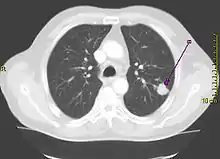

Рентгенограмма грудной клетки, демонстрирующая солитарный лёгочный узел в верхней доле левого лёгкого. | |

Солитарный лёгочный узел (одиночное периферическое образование) — в рентгенологии, периферическое образование в лёгочной ткани размером менее 3 см. Может быть случайной находкой на 0,2 % рентгенограмм грудной клетки[1] и около 1 % компьютерных томограмм[2].